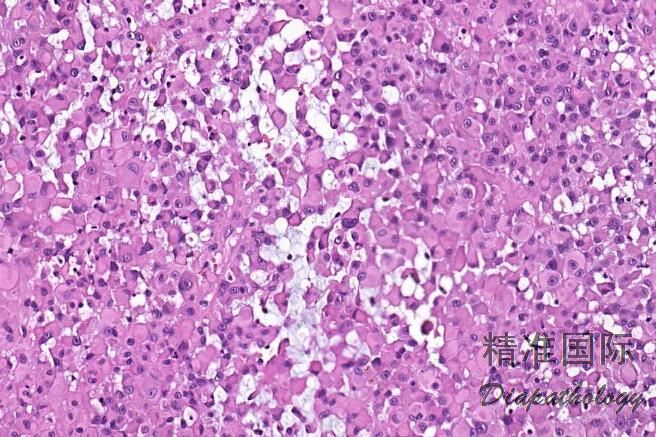

血管瘤样型:瘤细胞结节中央伴有明显的出血和囊性变,似扩张的血管;

经典型:

瘤细胞呈结节状或花环样排列,结节周围围绕胶原纤维,结节中央常伴有坏死;

肿瘤由上皮样细胞和梭形细胞共同组成,上皮样细胞呈多边形、卵圆形或胖梭形,胞质丰富,深嗜伊红色,和梭形细胞间有移行;细胞核轻度异型,呈空泡状,可见小核仁,核分裂像通常少于 5/10HPF;

间质可见嗜伊红色的胶原纤维;